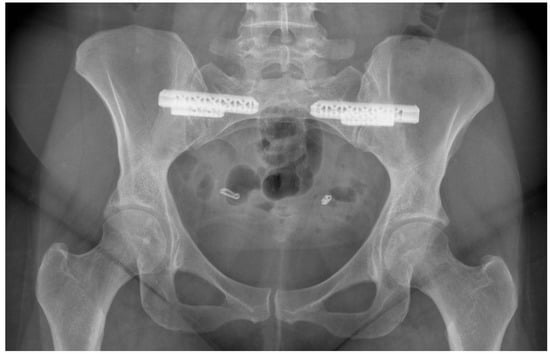

- Van Zwienen, C.M.; Van den Bosch, E.W.; Snijders, C.J.; Van Vugt, A.B. Triple pelvic ring fixation in patients with severe pregnancy-related low back and pelvic pain. Spine 2004, 29, 478–484. [Google Scholar] [CrossRef] [PubMed]